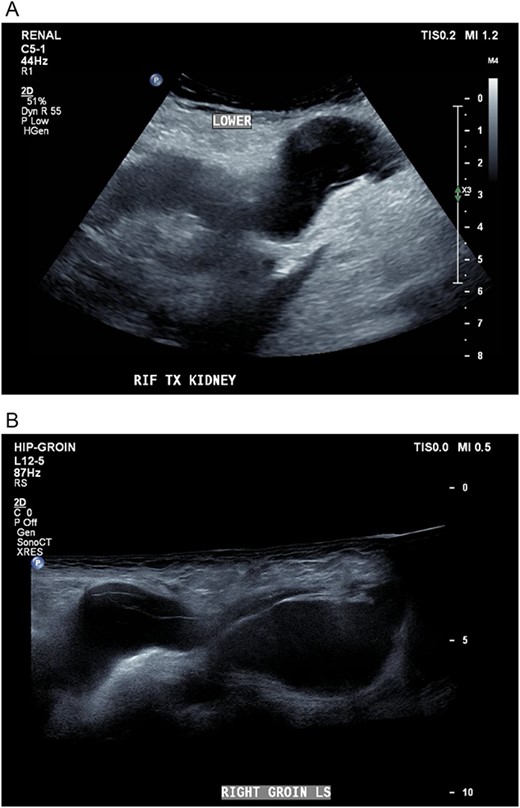

Three weeks postoperatively, the patient noticed a progressively enlarging right groin mass and associated discomfort. His examination was notable for a firm non-pulsatile non-reducible inguinal mass with no bowel sounds. He proceeded to have a CT Kidney, Ureter, Bladder (KUB), which revealed a small amount of perinephric collection (20 Hounsfield unit) marginating the posteromedial aspect of the transplant lower pole with a further fluid collection distending the right inguinal canal (10 Hounsfield unit) (see Fig. 1). The inguinal fluid pocket was localized with bedside ultrasound and 30 ml of clear fluid was aspirated with immediate symptom relief. The patient noticed reaccumulation of the fluid after a week and became symptomatic of pain again by the end of the third week.

Coronal CT image showing a dominant fluid collection extending off the lower pole of the transplant kidney into the right inguinal canal.